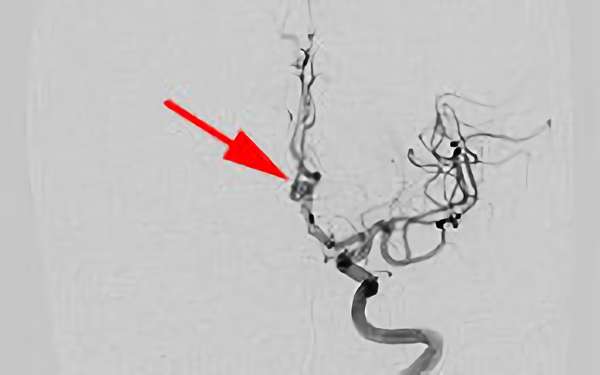

No.1631 手術中